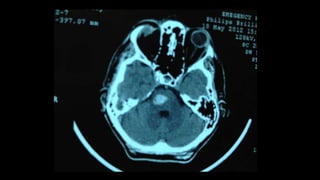

Quadriparesis: brain/high cervical cord MRI, with or

without contrast. Brain CT scan can also be used in the

acute setting; depending on the etiology, it may reveal

a diagnosis, e.g., pontine hemorrhage.

Other pareses? Quadriparesis: brain/highcervical cord MRI, with or without contrast. Brain CT scan can also be used in the acute setting; depending on the etiology, it may reveal a diagnosis, e.g., pontine hemorrhage. Other pareses: Beyond undergraduates!